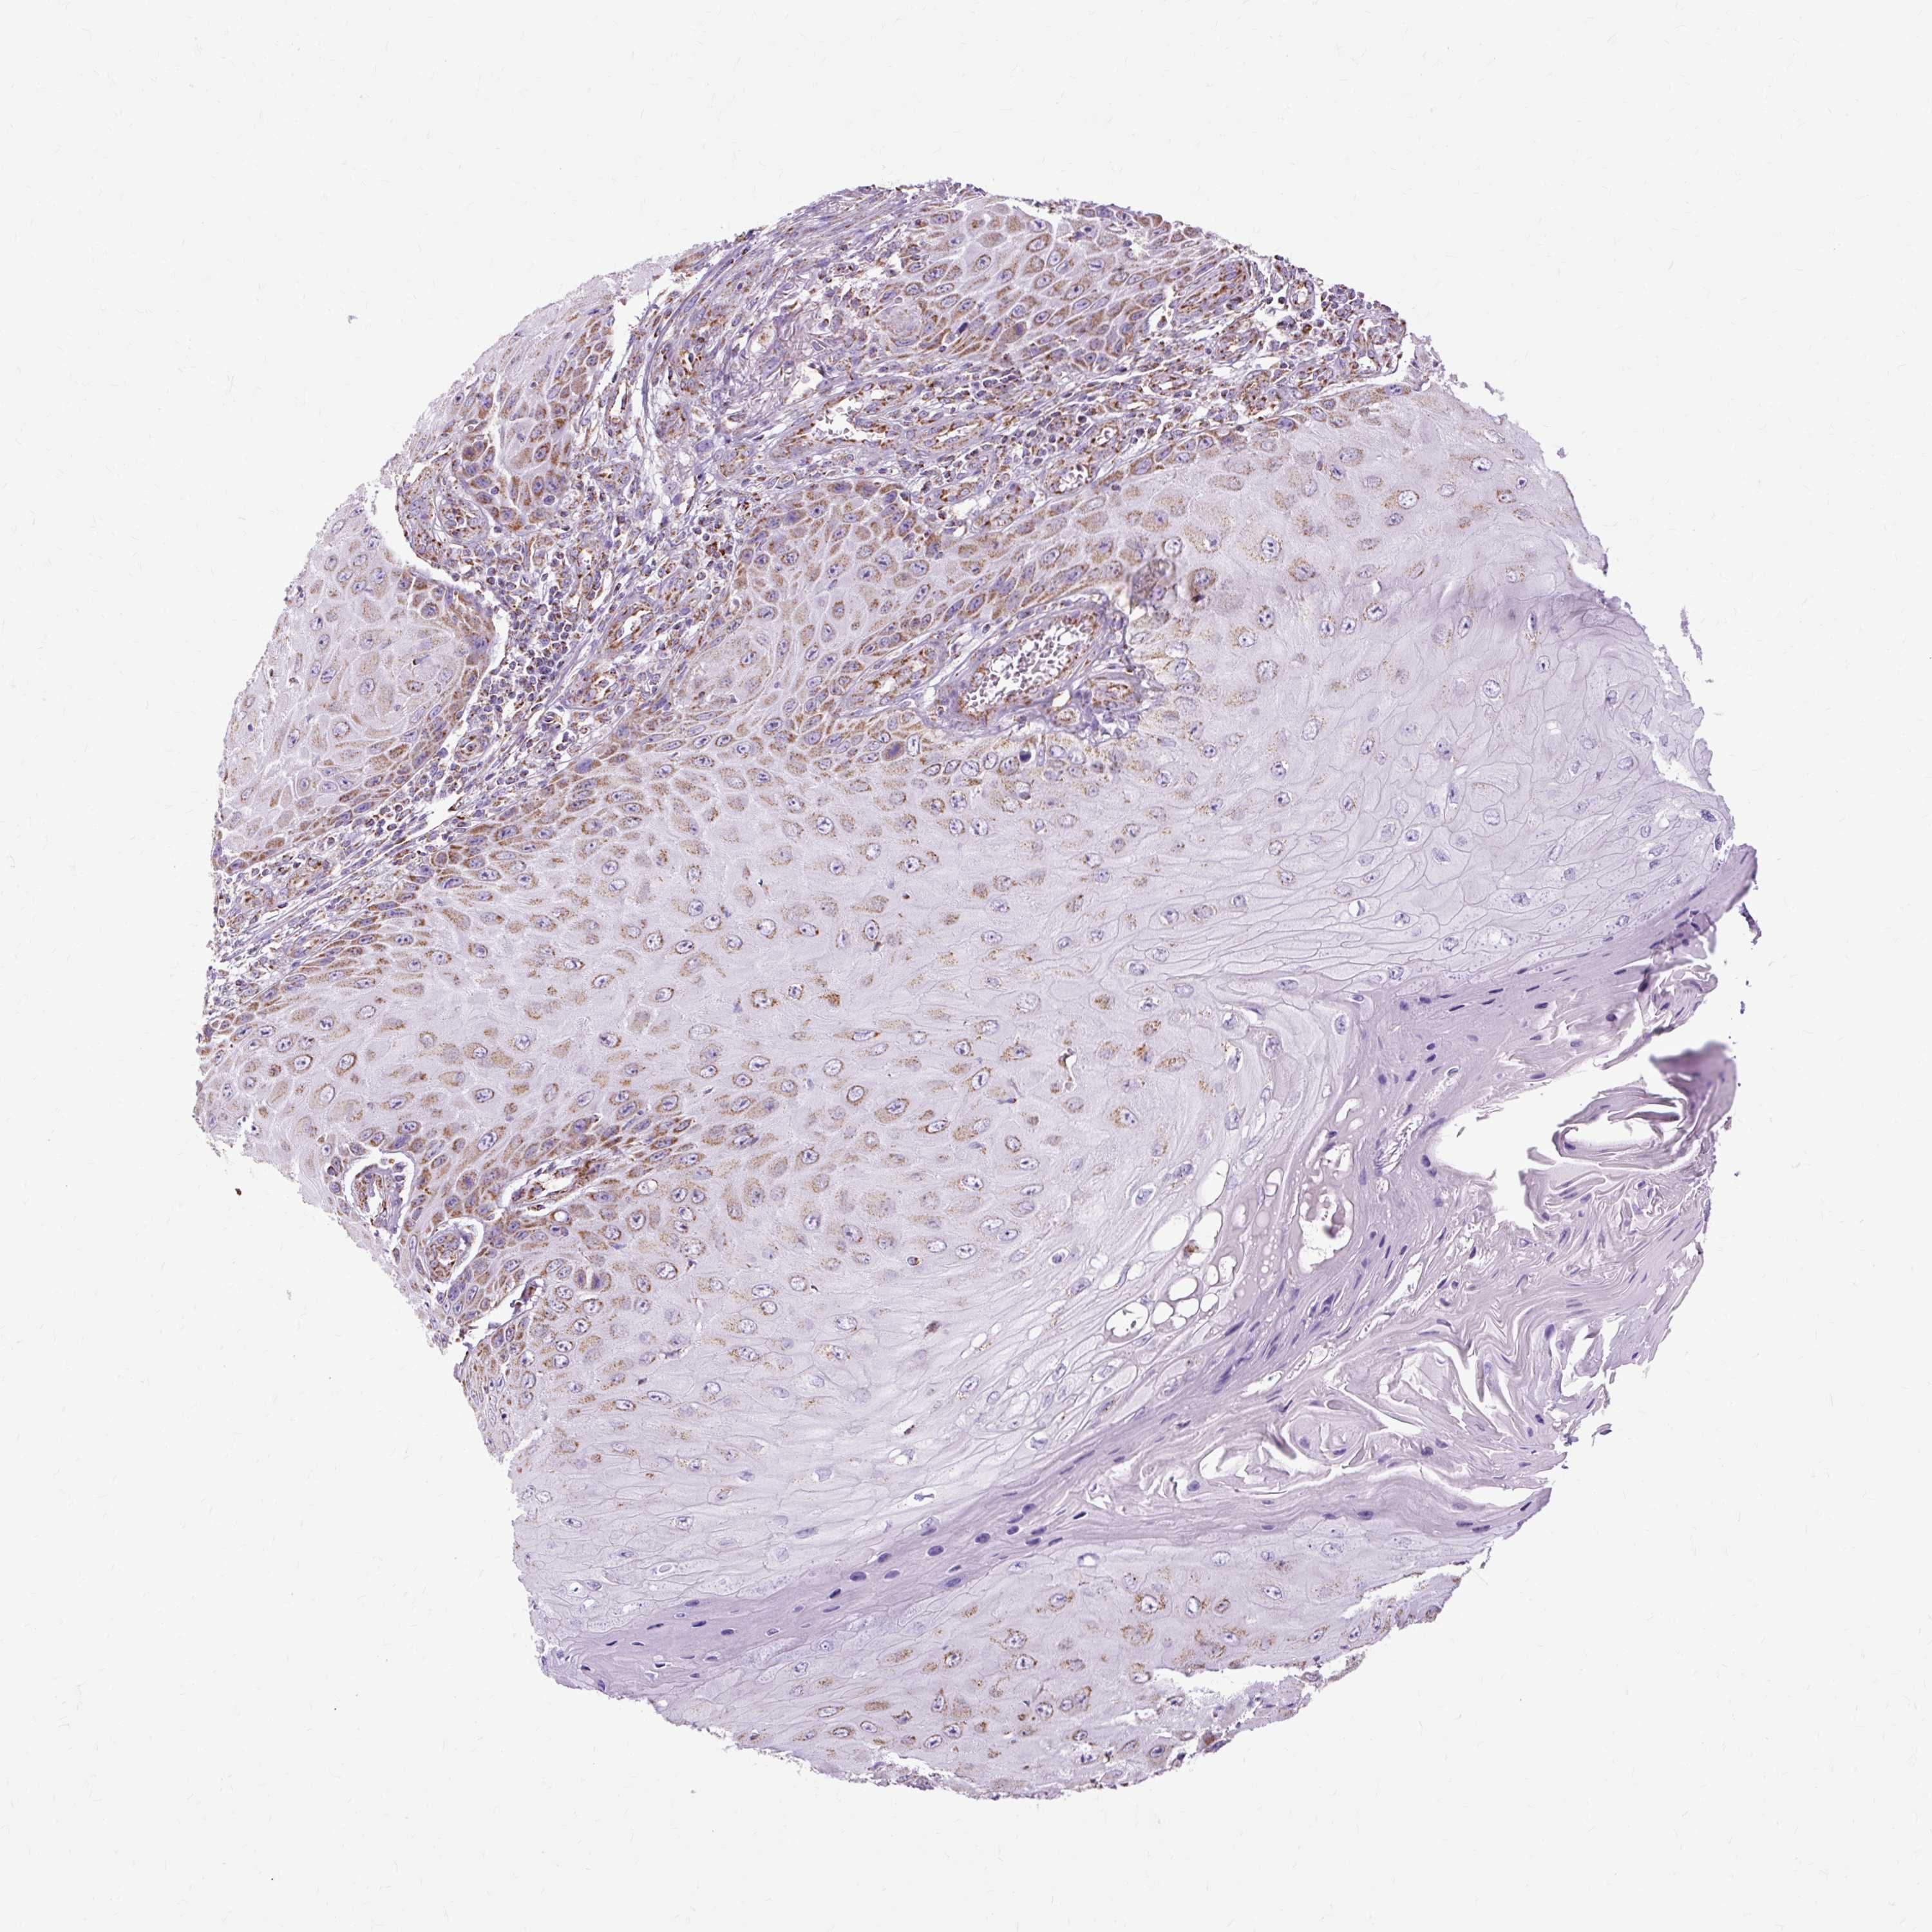

SKIN CANCER - Protein expressioni

A mouse-over function shows sample information and annotation data. Click on an image to view it in a full screen mode. Samples can be filtered based on level of antibody staining by selecting one or several of the following categories: high, medium, low and not detected. The assay and annotation is described here.

Antibody stainingi

Antibody staining in the annotated cell types in the current human tissue is reported as not detected, low, medium, or high, based on conventional immunohistochemistry profiling in selected tissues. This score is based on the combination of the staining intensity and fraction of stained cells.

Each image is clickable and will lead to virtual microscopy that enables deeper exploration of all samples and also displays staining intensity scores, fraction scores and subcellular localization as well as patient and tissue information for each sample.

Antibody HPA040786

Staining

High

Medium

Low

Not detected

Intensity

Strong

Moderate

Weak

Negative

Quantity

>75%

75%-25%

<25%

None

Location

Nuclear

Cytoplasmic/membranous

Cytoplasmic/membranous,nuclear

Squamous cell carcinoma, NOS